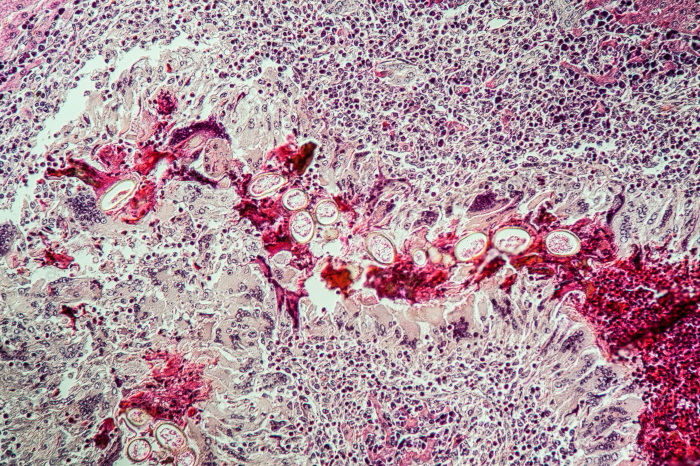

이 질환은 돼지고기 촌충(Taenia solium)의 유충이 사람의 뇌에 침투해 발생하는 심각한 기생충 감염병입니다.

신경낭미충증(Neurocysticercosis)은 돼지고기 촌충(Taenia solium)의 알이 사람의 몸에 들어와 유충 형태로 뇌에 침투해 발생하는 기생충 감염병이며, 주로 오염된 음식이나 물을 섭취하거나 덜 익힌 돼지고기를 먹을 때 감염될 수 있습니다.

일단 체내로 들어온 기생충 알은 소장에서 부화하여 혈액을 타고 뇌, 근육, 눈 등으로 이동합니다.

이 중 뇌로 유충이 이동하면 신경낭미충증이 발생합니다.